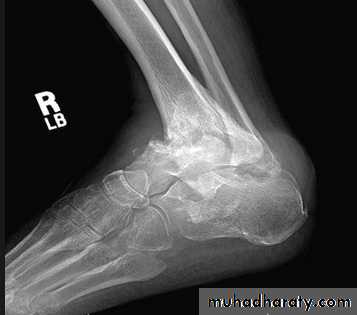

NEUROPATHIC ARTHRITIS (CHARCOT'S JOINT)

• Primary loss of sensation in a joint leads to arthropathy. Distribution helps determine etiology.• Causes

• Diabetes neuropathy: usually foot

• Radiographic features

• Common to all types

• *Joint instability: subluxation or dislocation

• *Prominent joint effusion

• --- Hypertrophic type, 20%

• Marked fragmentation of articular bone

• Much reactive bone

• --- Atrophic type, 40°/0

• Bone resorption of articular portion

• --- Combined type, 40%